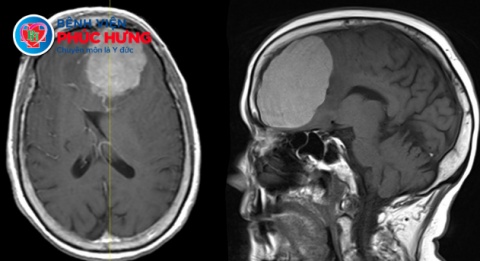

Qua thăm khám lâm sàng kết hợp các xét nghiệm cận lâm sàng cần thiết, các bác sĩ chẩn đoán bệnh nhân viêm màng não mủ với các biểu hiện điển hình gồm sốt cao – cứng gáy – suy giảm tri giác, đồng thời vẫn theo dõi để loại trừ nguy cơ đột quỵ não.

Kết quả chọc dịch não tủy cho thấy những đặc điểm điển hình của viêm màng não mũ:

- Dịch não tủy trắng đục

- Bạch cầu: 675 tế bào/uL (bình thường 0–5 tế bào/uL)

- Phản ứng Pandy dương tính